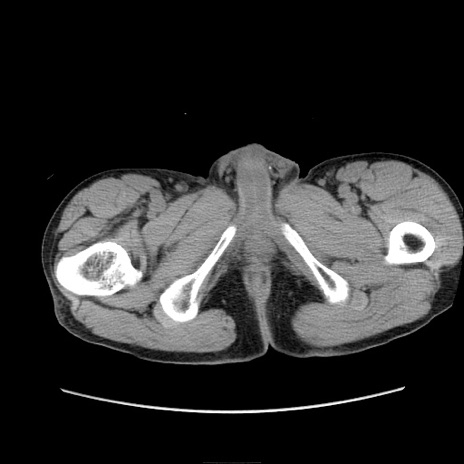

冠状断像

【症例】 60歳代男性

【主訴】 下腹部痛

【現病歴】 本日夜中より下腹部痛の症状認め、受診。

【既往歴】 膀胱癌(膀胱全摘+尿管皮膚瘻術) 、胃癌術後

【身体所見】 BT 35.3℃、PR 58/min、BP 136/98mHg、腹部平坦、軟、腸蠕動音±、ストマ留置あり、左上腹部~正中部に圧痛あり、反跳痛なし。

【データ】WBC 5100、CRP0.01